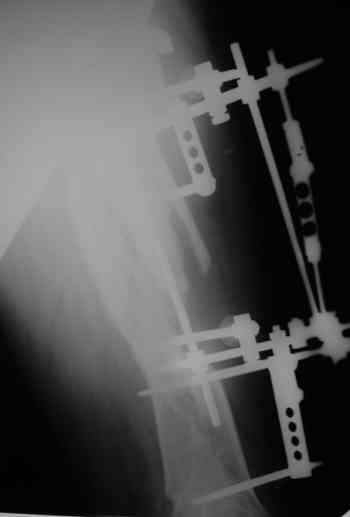

Уважаемые коллеги! Пришел на консультацию вот такой больной (первые 3-и рисунка). Травма автодорожная, апрель 2006г. Лечился консервативно, вытяжение и гипс. Через пять месяцев стал ходить. Укорочение бедра 6 см. 26 февраля 2007г. оступился, упал. Прооперирован в г.Баку - наложен стержневой аппарат. Ходит с костылями, наступая на левую ногу. Мы попросили что нибудь из ранних снимков. Принес рентгенограммы перелома (рис. 4,5). Посмотрели, наснимали сами (рис. 6-10). Похоже, что нет сращения нигде. Хотелось - бы обсудить следующие вопросы:1. дальнейшая тактика - реостеосинтез или подождать (ослабить аппарат, дать нагрузку и т.д.)?2. если реостеосинтез - то чем и как? Юрий Алексеевич Булахтин

Надо делать чрескожную подвертельную остеотомию, чтобы получился открытый клин. Проблемы будут и с формированием канала, надо развертки типа наших. Был как-то похожий случай, сделали одномоментно, сняли аппарат 5-месячый на столе, заштифтовали с подвертельной остеотомией (в приложении).